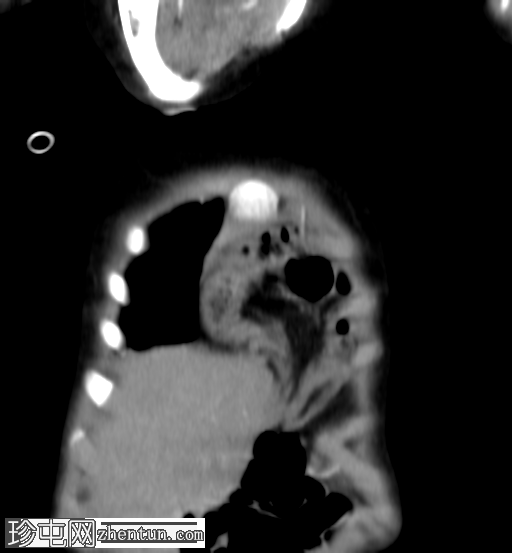

2.png

侧位片

底部可见边界不清的阴影,最符合呼吸道感染的表现。

正位和侧位片上偶然发现胸骨后肠管。